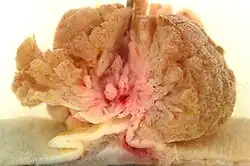

- Gross examination – the examination of diseased tissues with the naked eye. This is important especially for large tissue fragments, because the disease can often be visually identified. It is also at this step that the pathologist selects areas that will be processed for histopathology. The eye can sometimes be aided with a magnifying glass or a stereo microscope, especially when examining parasitic organisms.